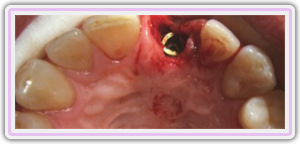

Healing Screw On The Impant

Immediate Implant Placement

Impression Of The Implant

Removal Of Tooth